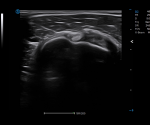

· HRI QA assesses hepatic steatosis by quantitative results with multiple sampling points available.

· Strain Elastography assists in analyzing tissue stiffness to detect potential abnormalities.